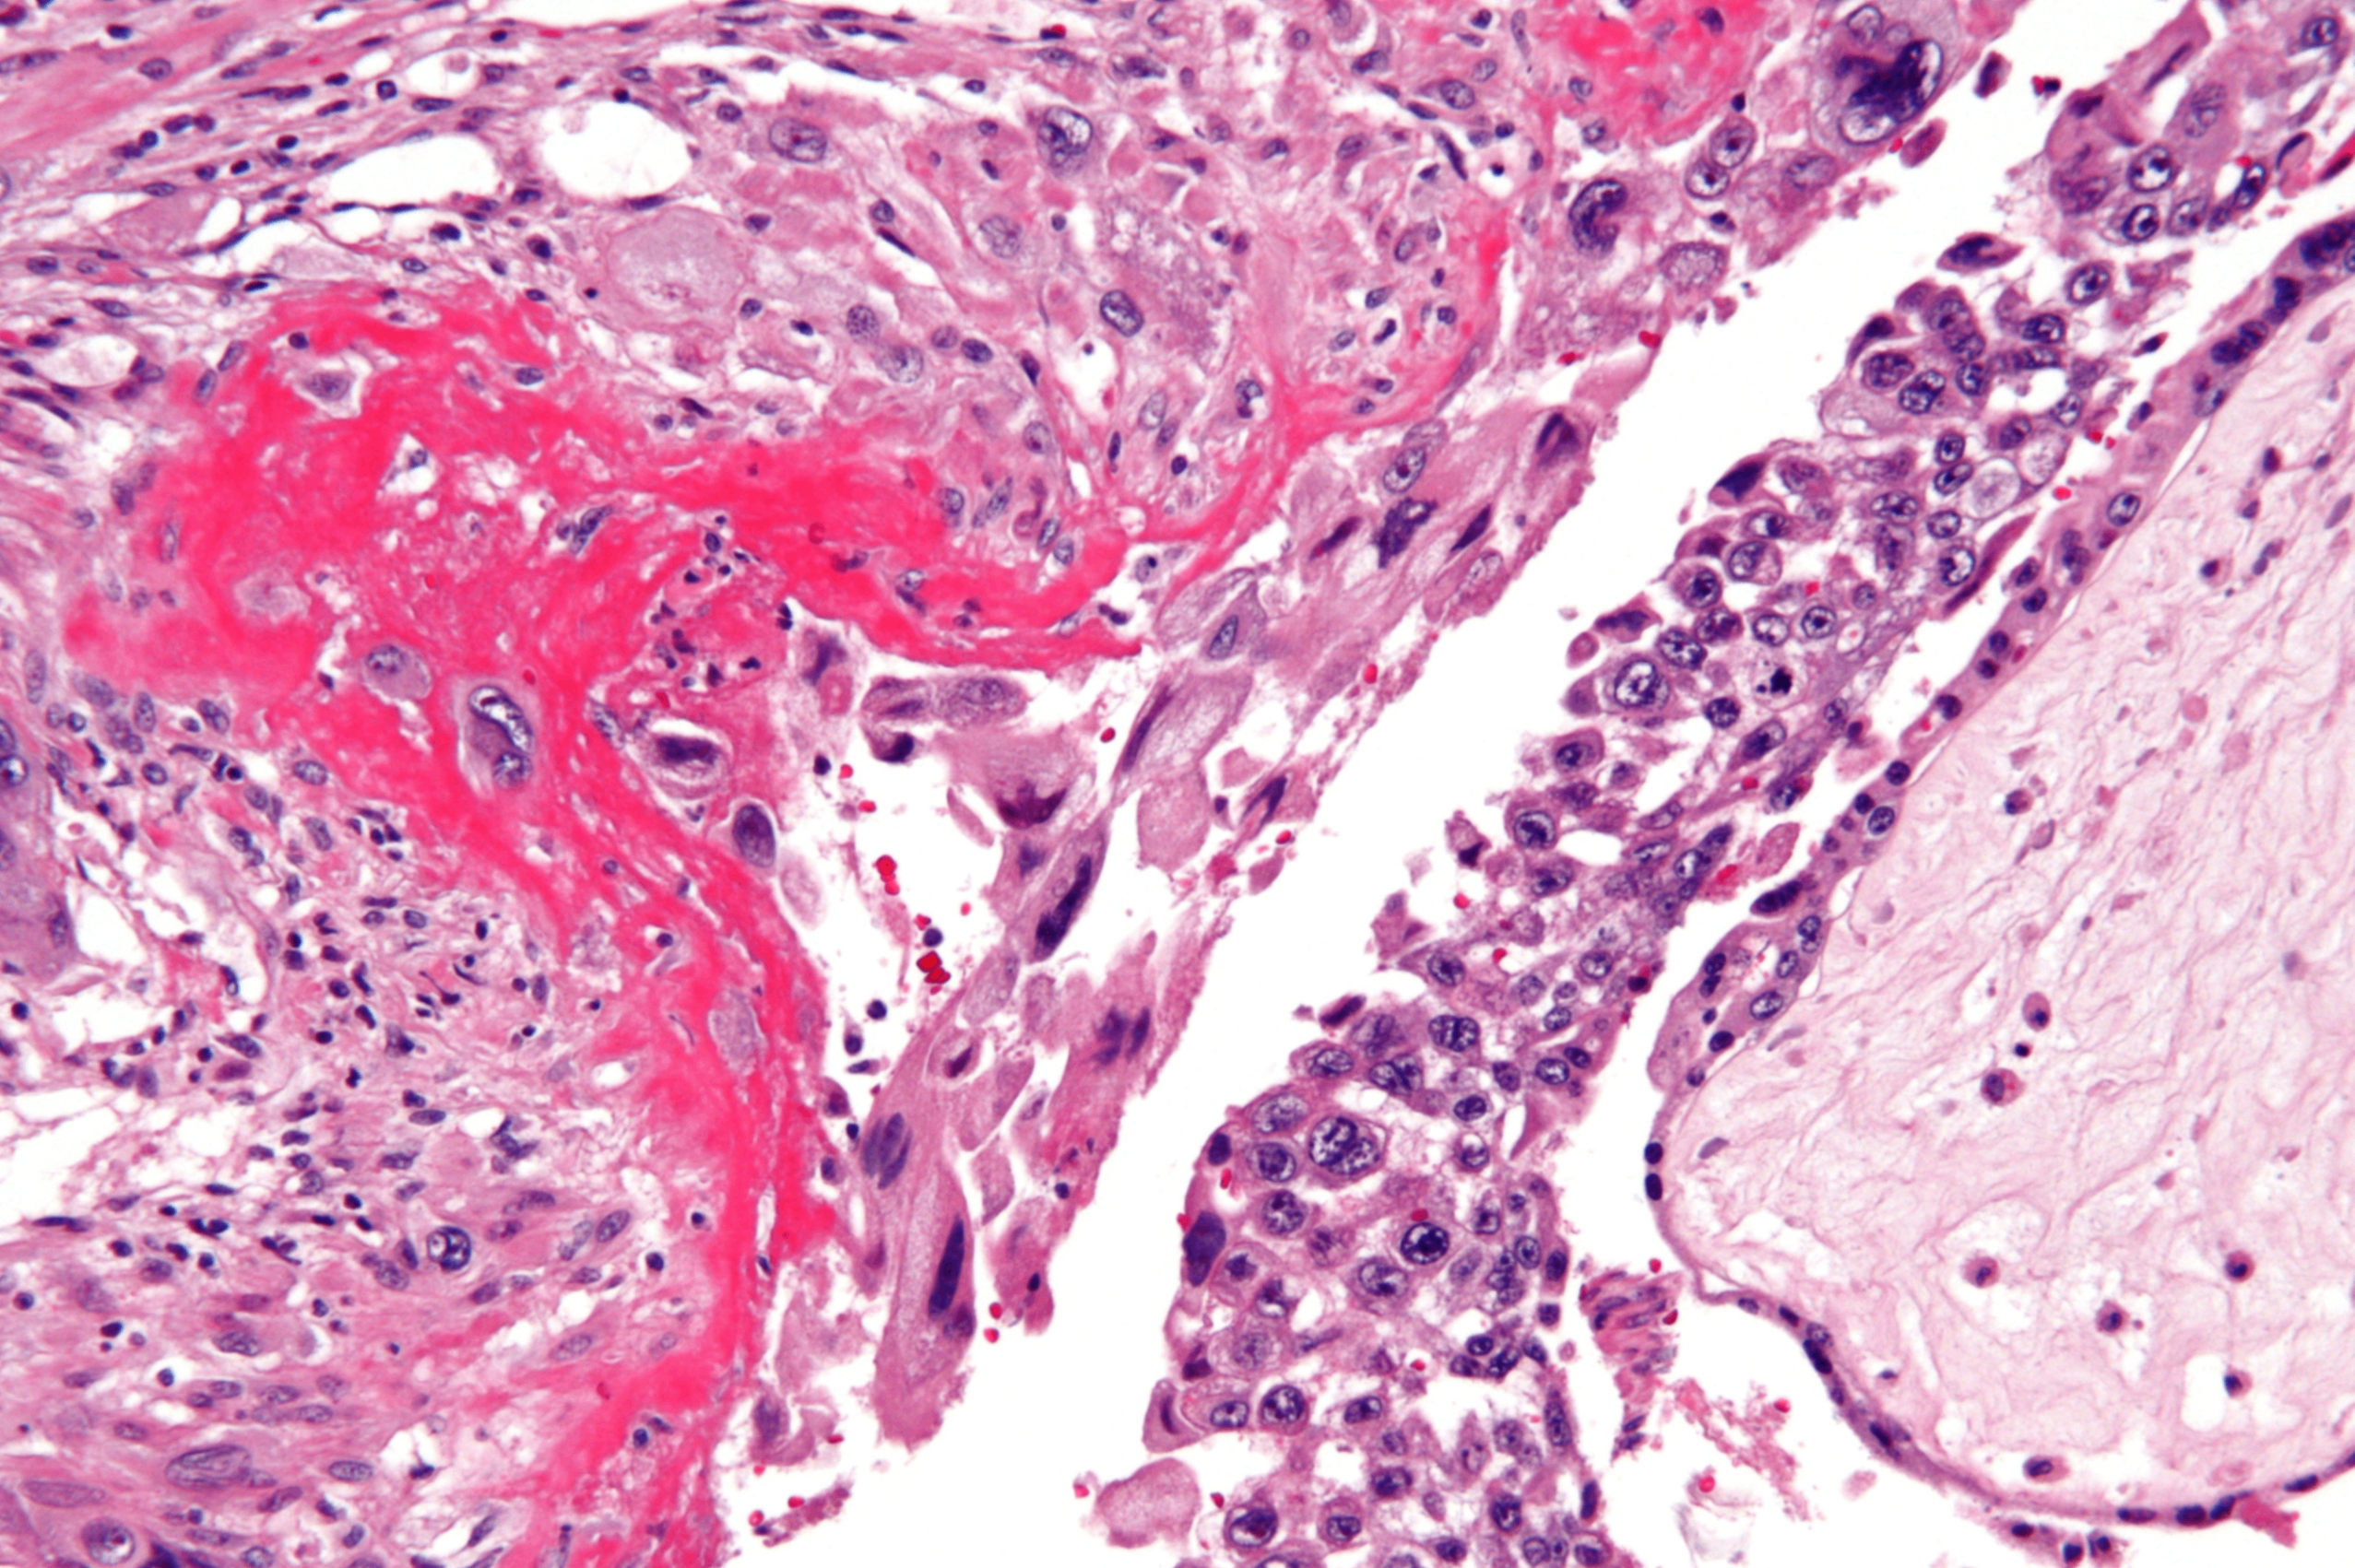

Invasive hydatidiform mole, Wikimedia Commons

3. 침윤기태 (invasive hydatidiform mole)

포기상태가 자궁근충까지 침윤

혈관 침범 및 전이 가능 (폐, 뇌 등)

• 질출혈 및 자궁 비대가 나타남

• 소파술로 포기상태 제거 후에도 지속적으로 높은 hCG 수치